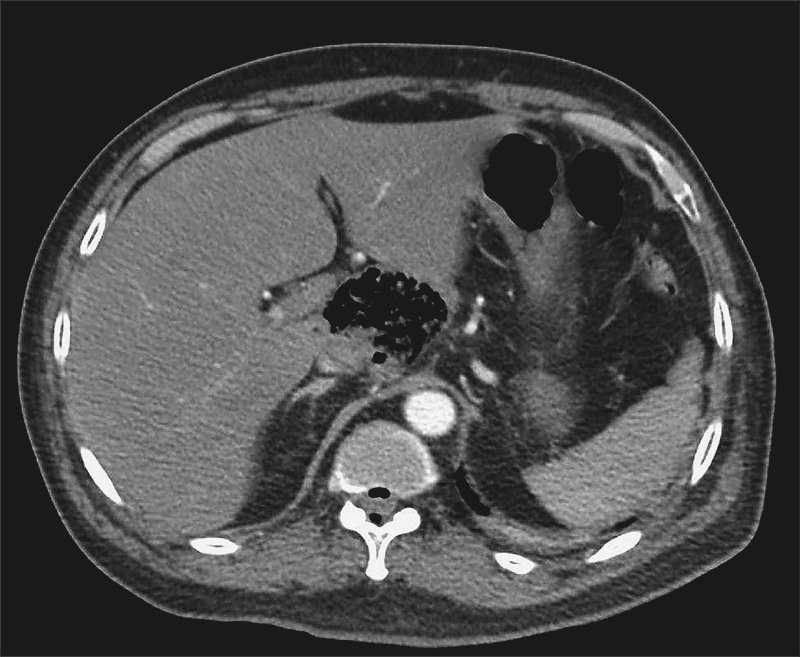

What is the diagnosis in this patient who presented with high fever? Image

A 60-year-old man of Burmese origin

👉 severe back pain that had lasted 1 week.

👉 fever (39.8°C) and hyperglycemia but had not received a diagnosis of diabetes previously.

Computed tomography of the abdomen reveals a gas-forming infection in the caudate lobe of the liver.

Cultures of material from percutaneous drainage of the liver abscess all grew Klebsiella pneumoniae. Image